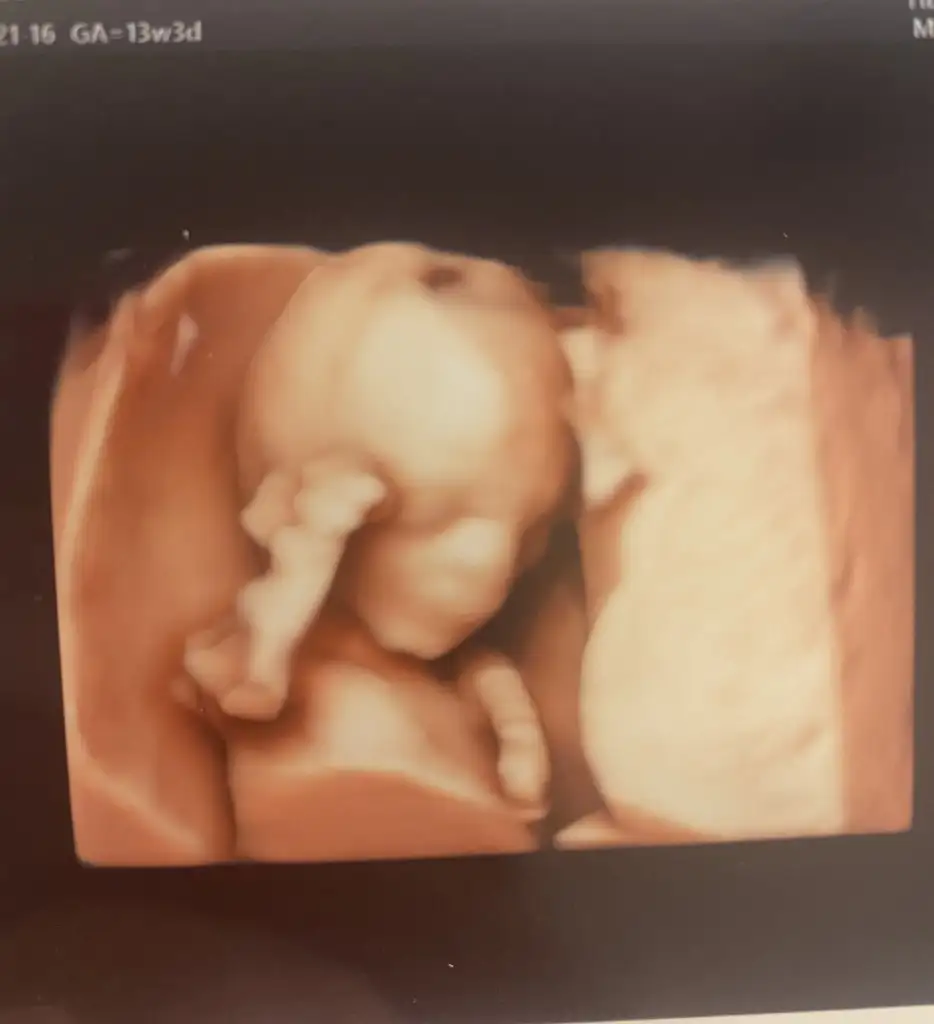

Herkese merhaba,aranıza yeni katıldım. Çok uzun süredir bu forumu takip ediyorum, şimdiye kadar bana haberiniz olmadan çok yardımcı oldunuz hem öğrendiğim çok şey oldu deneyimlerinizden, hem aynı mutluluk ve endişeleri başkalarının da yaşadığını bilmek yalnız hissetmemek çok iyi geldi. Rheaa Rheaa 'ya özelden bilgilerimi attım, size de miniğimin bir fotoğrafıyla merhaba demek teşekkür etmek istedim. Cinsiyeti erkekmiş bu arada.

Eklentiler

• IMG-0918.webp

IMG-0918.webp

12,6 KB · Görüntüleme: 98